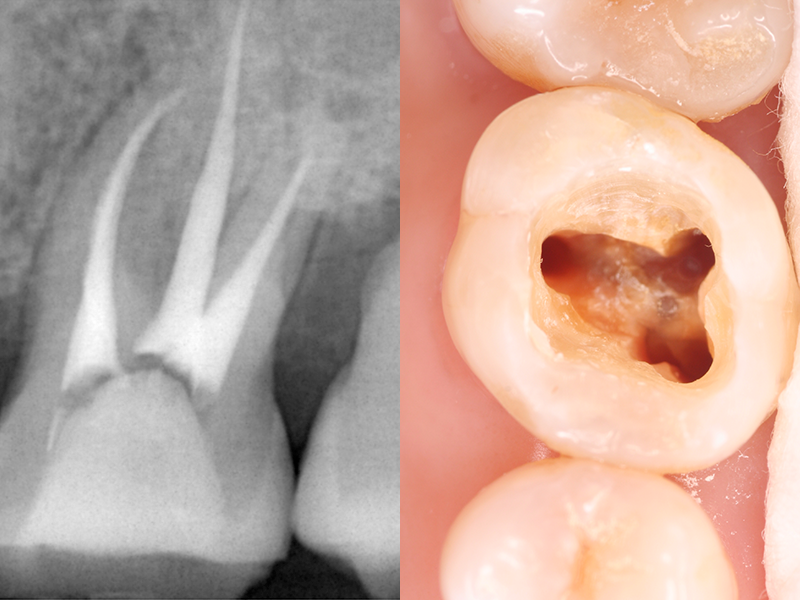

歯の内部には、神経や血管を含む「歯髄(しずい)」と呼ばれる組織が存在します。

むし歯の進行や外傷によってこの歯髄が細菌に感染したり、壊死したりした場合には、「根管治療」により歯髄を除去する必要があります。

むし歯菌に侵された根管内にある神経や血管を除去し、消毒のための薬剤を充填してから補綴物(ほてつぶつ)を装着することで、歯根を残す治療方法です。

根管治療用の器具を使い、感染している歯質や残っている歯髄などを除去します。